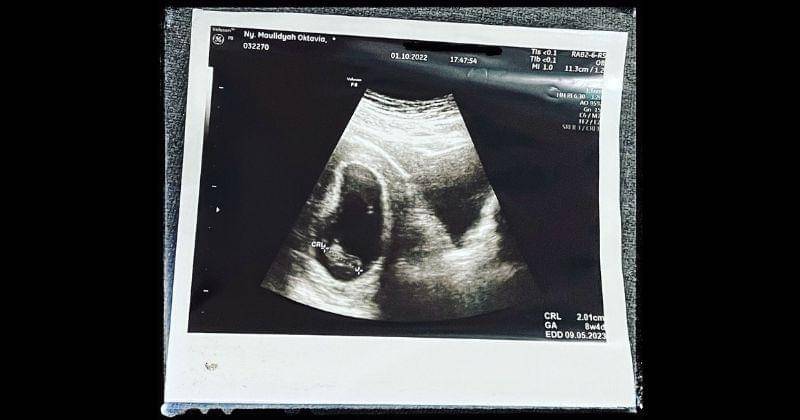

1. Janin Via Vallen berhenti berkembang di usia ke-8 minggu

Via dan suaminya itu menanti kehadiran anak pertama mereka dengan bersemangat. Janin di dalam kandungan Via Vallen sayangnya harus mendapatkan diagnosis buruk karena tidak berkembang di usia kehamilan ke-8 minggu.

"Tanggal 1 (Oktober) kemarin, Ami (sebutan Via Vallen untuk anaknya) dapet hadiah yang luar biasa menyakitkan. Di usiamu yang ke-8 minggu yang seharusnya detak dan gerakmu sudah bisa dideteksi melalui USG ini malah sunyi, hanya ada bentukmu tanpa adanya suara apapun," tutur Via di Instagramnya, 7 Oktober 2022.

"Menurut hitungan dokter, seharusnya usia kamu 12 minggu nak. Tetapi hasil USG menyatakan usia kamu masih 8 minggu (sama dengan hasil USG 1 Oktober 2022 kemarin)," kata Via.